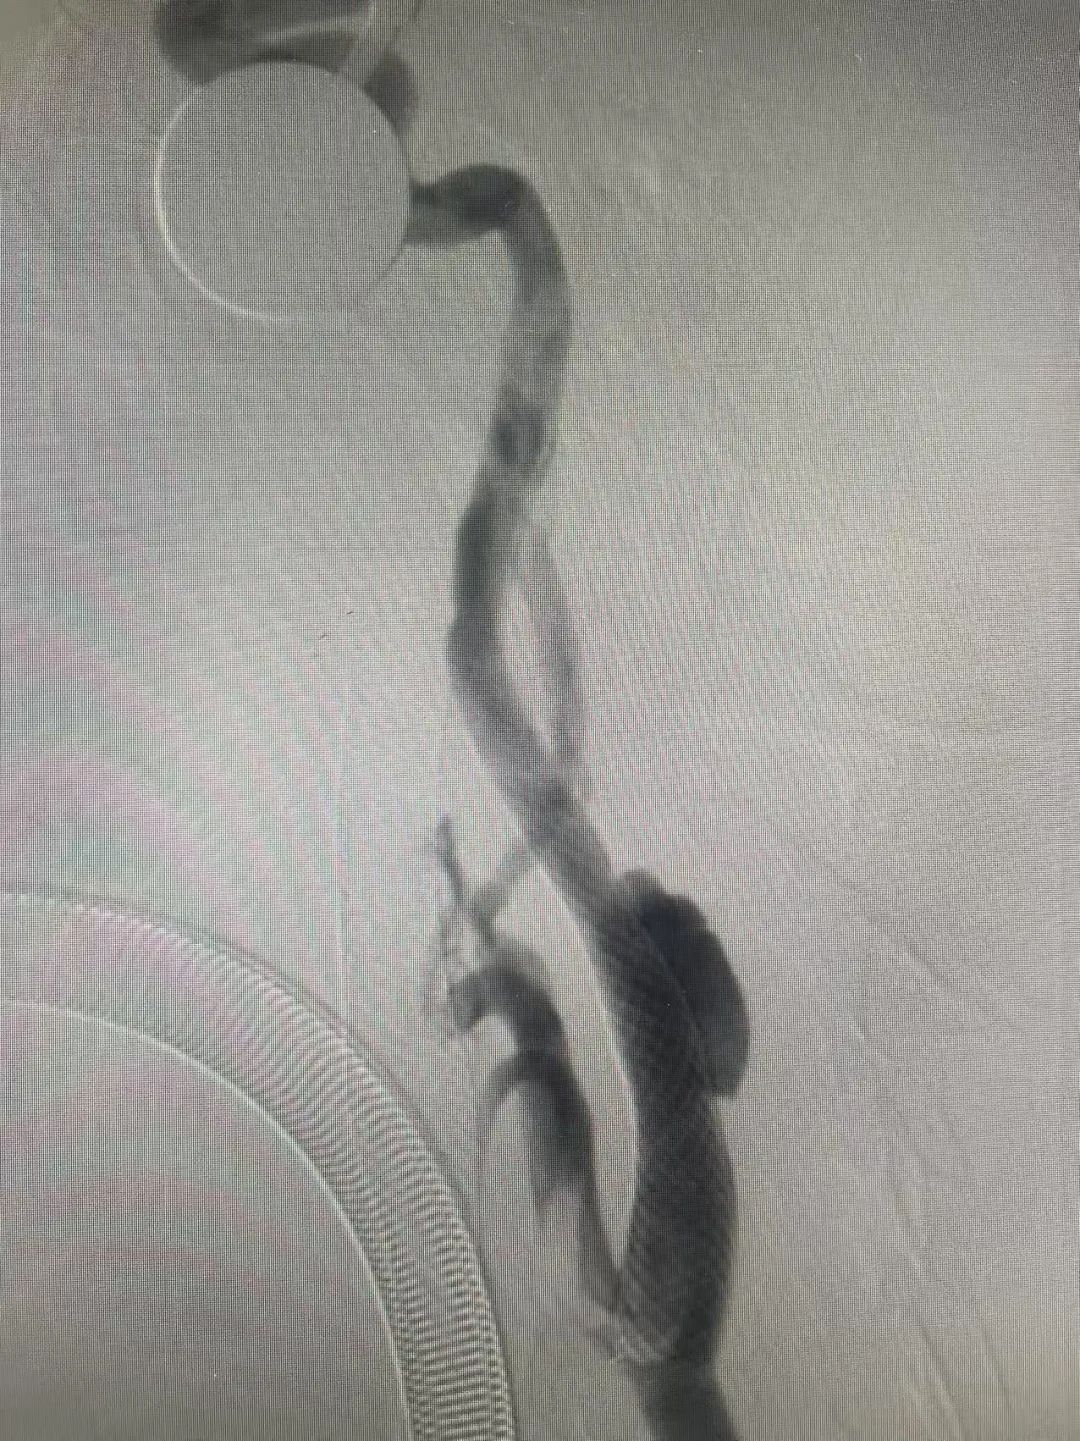

Y先生术前血管

Y先生术后血管